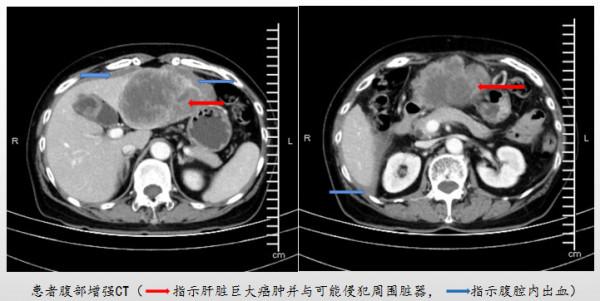

不久前,救護車將一位肚子劇烈疼痛、渾身直冒冷汗的老太太送到了上海市第十人民醫院急診。沒有明顯外傷卻如此痛苦,顯然問題嚴重。果然,醫生髮現患者血液中與原發性肝癌相關的腫瘤標誌物“甲胎蛋白”為強陽性,超過了1200ng/mL,CT檢查更是發現肝臟裡面長有一個直徑約12釐米的巨大腫瘤,佔據了左半肝並突破肝臟的包膜向腹腔內生長,且腫瘤已破裂出血。

時間在不斷流失,每拖延一小時,病人就要多冒一小時的生命危險。緊急時刻,肝膽胰外科、輸血科、麻醉科以及手術室立即形成聯動機制。外科病房密切觀察患者的生命體徵、血氧飽和度和血色素濃度等指標,並給予其輸注止血藥物、制動、腹帶加壓包紮等一系列保守治療措施。輸血科與市中心血站反覆溝通,終於在患者入院後第二日下午申請到術中備用血。手術室和麻醉科立即開放綠色通道,當天晚上6點,周阿婆被送進手術室。李俊主任團隊開啟患者的腹腔,發現裡面已有約600ml的積血塊,經過長達5小時的“浴血奮戰”,最終完整切除了肝臟上的巨大腫瘤,清除了血塊,並用大量蒸餾水儘可能把腹腔內沖洗乾淨。